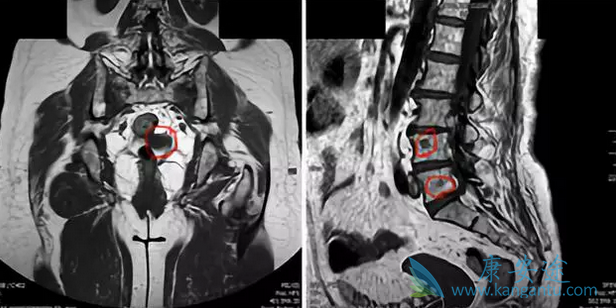

012年7月,一个55岁的女性确诊为左侧局部晚期乳腺癌,激素受体阳性、HER2阴性,先做了8个疗程的新辅助化疗,然后做了彻底的手术、术后的放疗。然后,接受阿那曲唑内分泌治疗——这一系列安排,都是常规的普通治疗。2015年3月,右侧腋窝淋巴结肿瘤复发,穿刺证实是肿瘤转移。于是,开始接受传统方案的化疗:长春瑞滨、顺铂、5-Fu。2015年12月,多发骨转移。下图红圈,显示的就是病灶的部位。由于这些骨转移,患者疼痛明显,依靠止痛药镇痛,晚上依然无法入睡。

这时候,该癌症患者并没有去追逐新药或者新的临床试验,2016年1月开始,她尝试又一种化疗药:艾日布林;同时对疼痛最明显的骨转移病灶做了放疗。艾日布林联合骨转移放射治疗后,患者症状明显患者缓解,肿瘤逐步缩小。2016年11月,全面复查发现,患者全身的病灶已经完全消失,症状完全缓解——截止到2018年3月,患者依然维持着无瘤状态,健康生活。